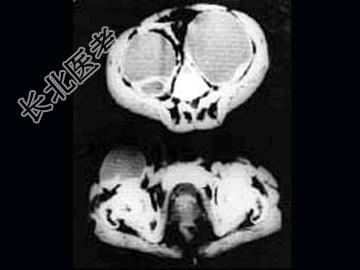

- 单项选择题女,34岁, 咳嗽,腰背疼痛二年, CT检查如图,最可能的诊断是 ( )

A、结核性脓肿

B、囊肿

C、淋巴管瘤

D、卵巢囊肿

E、卵巢囊腺瘤